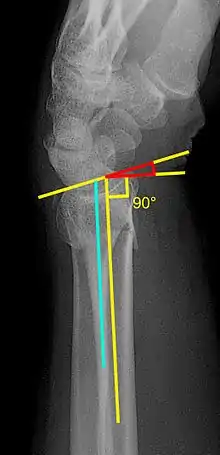

- Volar or dorsal tilt - A line is drawn joining the most distal ends of the volar and dorsal side of the radius. Another line perpendicular to the longitudinal axis of the radius is drawn. The angle between the two lines is the angle of volar or dorsal tilt of the wrist. Measurement of volar or dorsal tilt should be made in true lateral view of the wrist because pronation of the forearm reduces the volar tilt and supination increases it. When dorsal tilt is more than 11 degrees, it is associated with loss of grip strength and loss of wrist flexion.[5]

- Radial inclination - It is the angle between a line drawn from the radial styloid to the medial end of the articular surface of the radius and a line drawn perpendicular to the long axis of the radius. Loss of radial inclination is associated with loss of grip strength.[5]

- Radial length - It is the vertical distance in millimetres between a line tangential to the articular surface of the ulna and a tangential line drawn at the most distal point of radius (radial styloid). Shortening of radial length more than 4mm is associated with wrist pain.[5]

- Ulnar variance - It is the vertical distance between a horizontal line parallel to the articular surface of the radius and another horizontal line drawn parallel to the articular surface of the ulnar head. Positive ulnar variance (ulna appears longer than radius) disturbs the integrity of triangular fibrocartilage complex and is associated with loss of grip strength and wrist pain.[5]